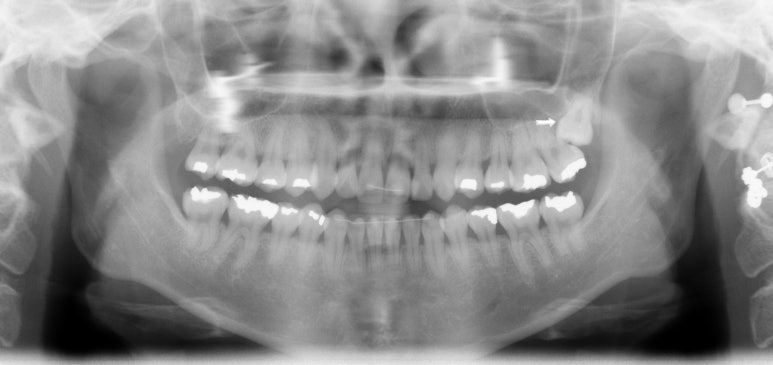

60대 환자분이 이런얘기를 하면 10년 전만해도 불편한 것도 없으신데 굳이 교정을 하셔야할까요? 넌지시 물었었다. 근데 나도 나이가 들면서 이런 생각을 한다. 왜? 나이가 들어서 보기 싫은 건 더 고쳐서 더 자신있게 예쁘게 건강하게 살고 싶은걸.. 니들이 뭘 안다고

그런것 같다. 그래서 네 그게 불만이고 콤플렉스라면 앞니만 간단히 6-7개월 투자하셔서 (당연히 이점이 있다) 대신 그 불편한 기간은 잘 견뎌주셔야 한다고

대부분의 환자분들은 예뻐지는 내 이를 직접보니 잘 견디시는 것 같다.

발치 전 사진이 없어서 아쉽지만... 이렇게 한 개 치아를 반드시 발치해야하고 주변치아들이 비뚤다면 정말 교정이 답이 될 수 있다는 생각이 든다. 잇몸이 너무 좋지 않아서 잇몸공간이 눈에 띄기는 하지만 이후 치주 관리도 잘하시고 유지장치로 앞니끼리 고정되어 있으니 예상보다 오래 잘 쓰시고 계신다..